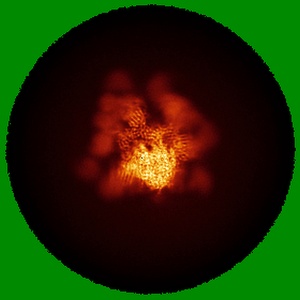

SARS-CoV-2 spike trimer (6P) in complex with three H18 and three R1-32 Fabs

Single-particle3.39 Å

Sample: SARS-CoV-2 spike trimer (6P) in complex with three H18 and three R1-32 Fabs